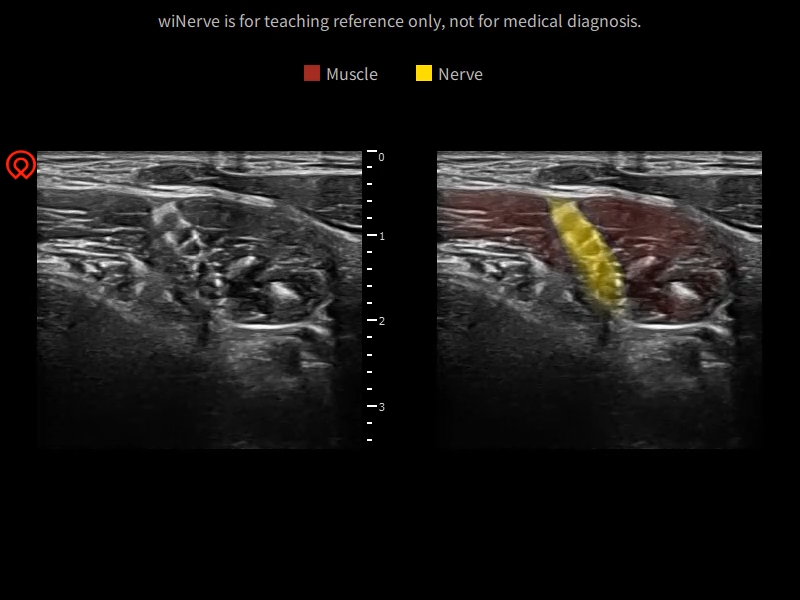

wiNerve - riconoscimento intelligente dei nervi supporto di multi nervi

Riconoscimentoin tempo reale

Supporto di pit nervi